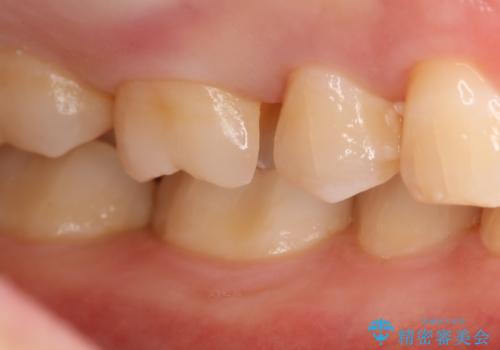

- 右上6番の虫歯治療を主訴に来院された患者様です。

切削量・形態を考慮し、セラミックインレーでの治療を計画しました。

保険の材料が劣化し中で虫歯が進行していたので、全て取り除いた上で形を整え型をとりインレーをセットしています。